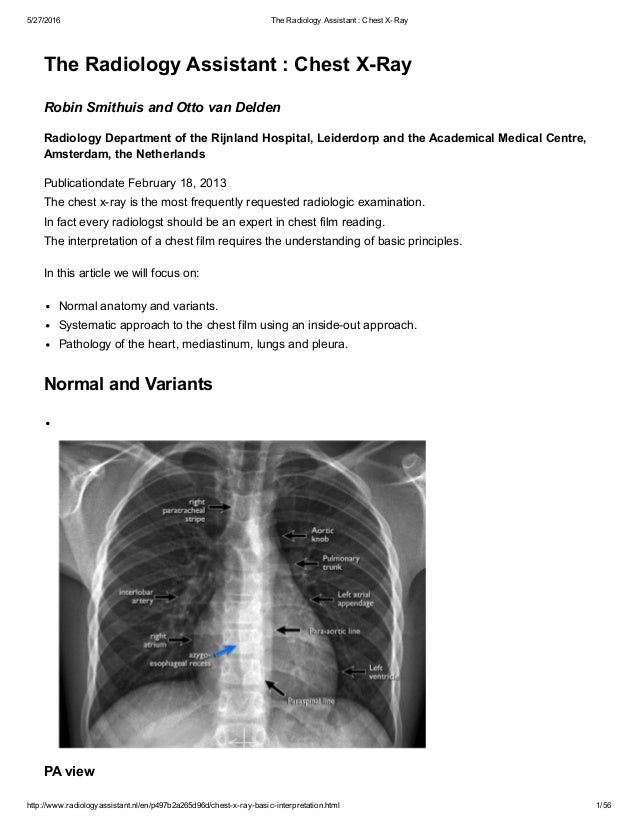

Knee Anatomy Radiology Assistant Gallery - How To Guide via ccuart.org

Knee Anatomy Radiology Assistant Gallery - How To Guide